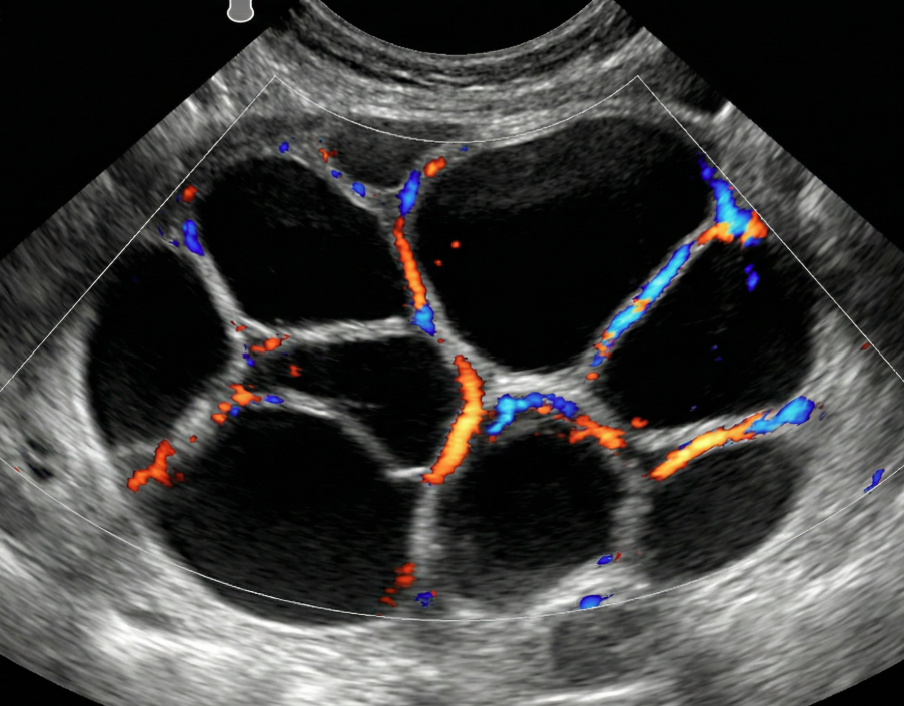

Risco: 10-<50%Cisto multilocular sem componente sólido ≥ 10 cm ou com IC = 4, cisto unilocular/multilocular com componente sólido, lesão sólida com superfície lisa e IC = 2–3.

Cisto multilocular, sem componente sólido

Cisto multilocular com componente sólido

Opções de imagem incluem US com especialista (se disponível) e RM (com O-RADS MRI score), de acordo com o protocolo do ginecologista-oncologista. Atendimento pelo ginecologista com consulta ao ginecologista-oncologista ou exclusivamente pelo ginecologista-oncologista.